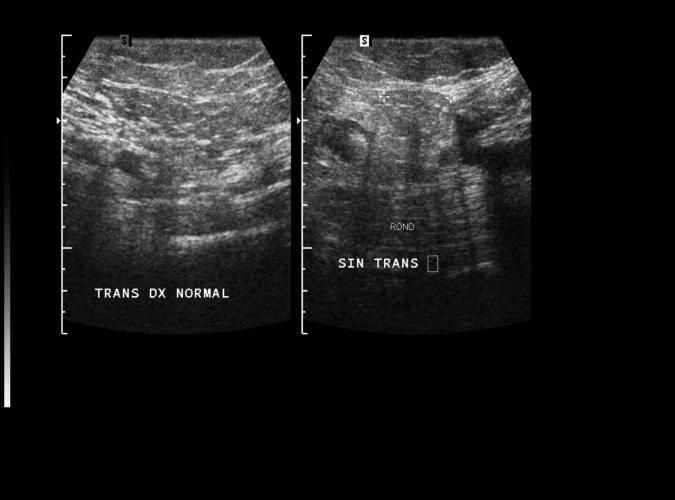

av Catherine Olsson, sonograf

Patologi.

Long. 45årig med vänstersidig testistumör.